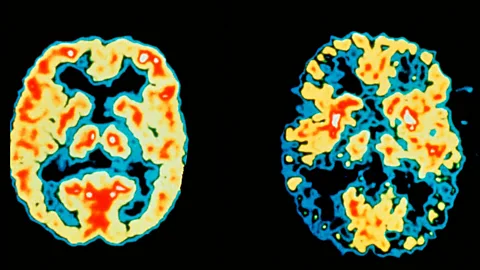

Over the past several years, there has been emerging evidence illustrating the importance of sleep in diminishing age-related memory loss and progression to mild cognitive impairment and dementia. Animal studies have shown that sleep allows clearance from the brain of waste products such as amyloid. An accumulation of amyloid plaques is considered one of the pathological hallmarks of Alzheimer’s dementia. There is much interest in this recently recognized sleep-related “brain washing” function of removing toxic products from the brain.

Science Photo LibraryThere are countless research studies that demonstrate decreased performance on a variety of brain cognitive measures following sleep deprivation. These have included measures of attention, emotional regulation, learning and memory, and “executive functions".